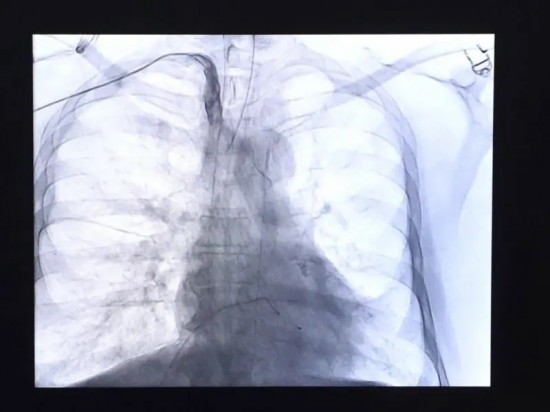

Enfermedades del corazón se mantienen como la primera causa de muerte en los mexicanos.

Con 100 mil 710 decesos durante el primer semestre del 2024, las enfermedades del corazón se mantuvieron como la principal causa de muerte de los mexicanos.

Ciudad de México.- Con 100 mil 710 decesos durante el primer semestre del 2024, las enfermedades del corazón se mantuvieron como la principal causa de muerte de los mexicanos.